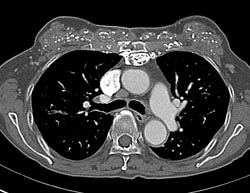

Diagnosis

Abscess and Cellulitis